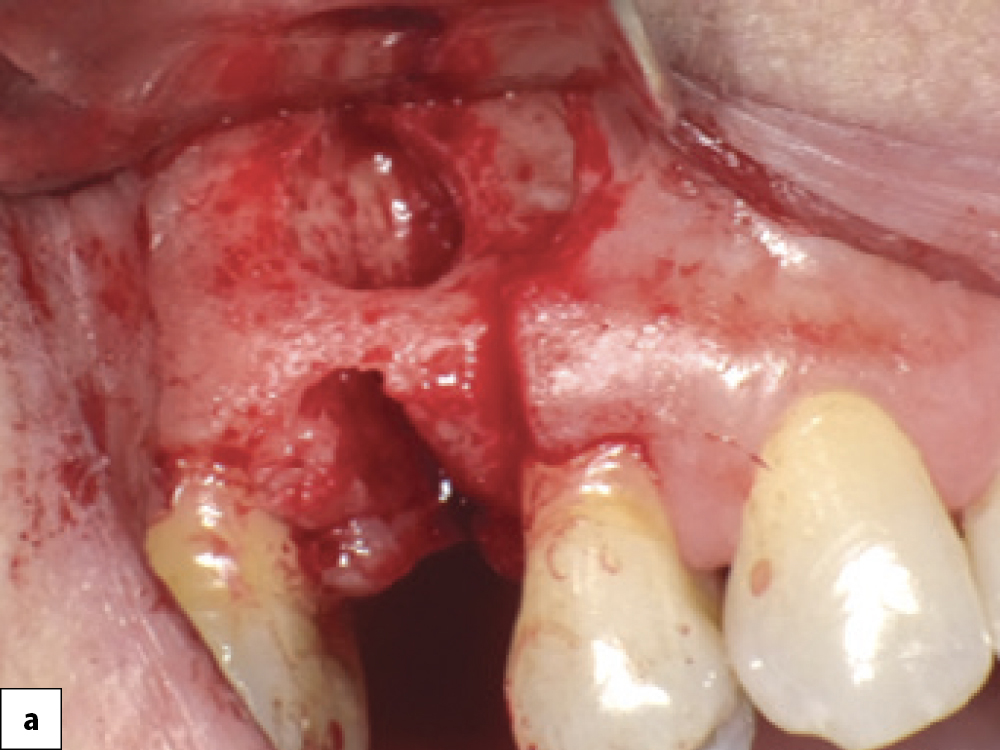

Bony Defect Evaluation A

Bony defect evaluation: (a) Flap reflection allows the clinician to visually evaluate the size and location of the fenestration to determine whether the defect will compromise implant positioning or primary stability when immediate implant placement is desired; (b) Examples of a large fenestration (green arrow) and loss of the buccal plate (blue arrow), either of which would contraindicate immediate implant placement due to the inability to obtain primary stability; (c) Additional example of flap reflection to show the fenestration.